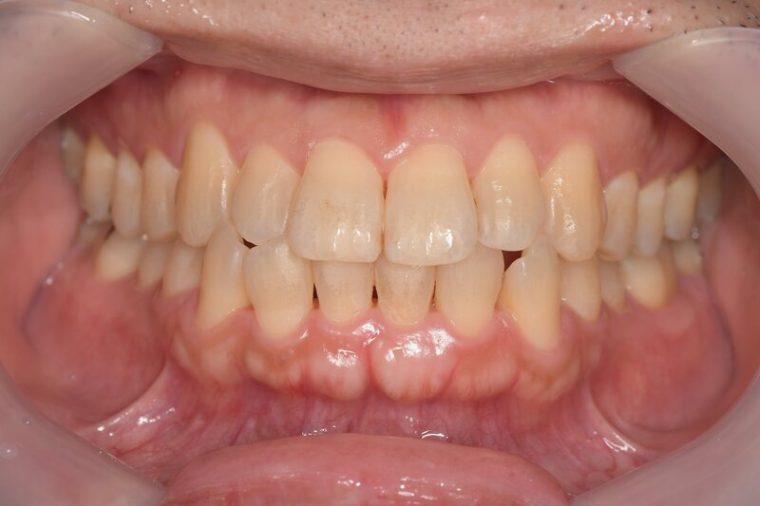

症例2

Before

症例

after

歯周病検査(治療前)

歯周病検査(治療後)

レントゲン写真

基本情報

年齢・性別 41歳・男性

主訴 主訴:歯ぐきから出血する

治療部位:全顎

治療内容 1.歯周ポケット検査、資料取り(レントゲン写真14枚・口腔内写真)、歯磨き指導

2.歯磨き指導チェック、縁上の歯石除去

3.縁下の歯石除去4回

4.再評価(歯周ポケット検査・レントゲン写真14枚・口腔内写真)

5.メインテナンス

治療期間 1日

治療費 合計:14,160円

内訳(全て保険診療3割負担)

・初診検査、歯磨き指導、縁上の歯石除去:3,630円

・レントゲン写真、縁下の歯石除去①:3,040円

・縁下の歯石除去②:1,530円

・歯磨き指導チェック、縁下の歯石除去③:2,070円

・縁下の歯石除去④:1,530円

・再評価:2,360円

(2022年5月現在現在)

リスク・副作用 ・歯石除去後すぐは歯ぐきを触っているため歯ぐきに違和感や痛みを感じる場合がある

・歯石除去により今まで腫れていた歯ぐきが引き締まり歯ぐきが下がる可能性がある

・歯ぐきが引き締まって下がることにより歯面が今までより露出し知覚過敏の症状がでる可能性がある

・歯石除去後、歯磨きを怠ると細菌が歯周ポケットのより深部まで入ってしまうため歯周病が悪化してしまう可能性がある

・一度歯周病になると再発しやすい為、定期的なメインテナンスが必要になります

治療方針 1.歯磨き指導

2.歯ぐき上の歯石除去

3.歯ぐき下の歯石除去

4.再評価

5.定期的なメインテナンス

特記事項 ・着色除去(PMTC)は自費治療のため希望しませんでした。

・右下7番の歯周ポケット5mmは親知らずの関係もあり、このまま維持していくことを説明しています。

・他4mmの歯周ポケットに関しては歯垢が少し残っていた為、再度歯磨き指導と、縁下の歯石を確認して様子をみることにしました。

担当者所見 全体的に出血が見られたのと、奥の歯ぐきは炎症があり歯周ポケットが深かった為、まずは歯ブラシの当て方+歯間ブラシ3Sサイズを使用して頂き炎症を落ち着かせました。

両方毎日使用して頂いた為、スムーズに歯周病治療を行うことができました。毎日のホームケアが不十分だと、なかなか結果に繋がらず、治療期間も長くかかってしまう為、患者様の協力が歯周病治療を成功させるためにはかなり重要になっていきます。

そして一度病気になった歯ぐきは再発しやすい為、今後は3ヶ月に1度の定期的なメインテナンスで、この状態を維持できるよう一緒に管理していきます。